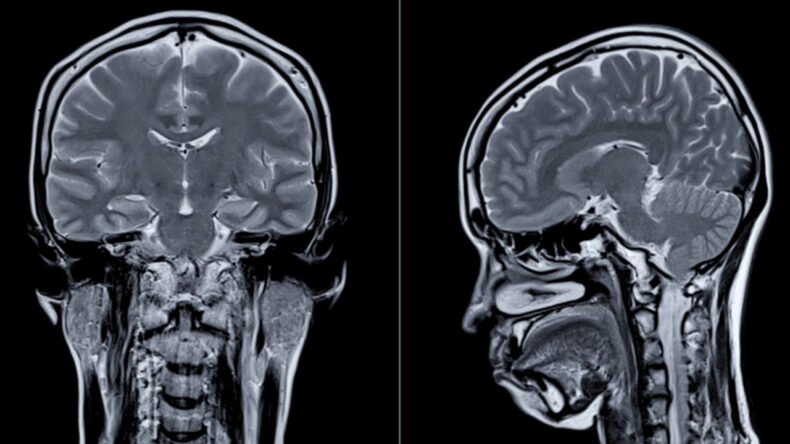

17 ile 95 yaş arasındaki 4726 bireyin 12 binden fazla beyin taramasının incelendiği araştırmada, cinsiyetler arasında “küçük ama sistematik farklılıklar” belirlendi.

Araştırma ekibi, katılımcıların tamamını en az iki kez MR taramasından geçirdi. Ortalama üç yıl aralıklarla yapılan bu taramalar sayesinde yaşlanmaya bağlı değişimlerin gözlemlenmesi sağlandı.

Böylece beyin hacmi, yüzey alanı, korteks kalınlığı, gri ve beyaz madde oranı gibi birçok değişken detaylı bir şekilde incelendi. Bu çalışma, bu alanda şimdiye kadar gerçekleştirilmiş en kapsamlı araştırmalardan biri olarak kaydedildi.